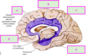

Label the arteries that supply A-C [3]

A = anterior cerebral artery (upper

and medial parts of the cortex)

(orange)

B = middle cerebral artery (lateral

areas of the frontal, parietal, and

temporal lobes) (white)

C = posterior cerebral artery (occipital

lobe and inferior parts of the

temporal lobe) (blue)